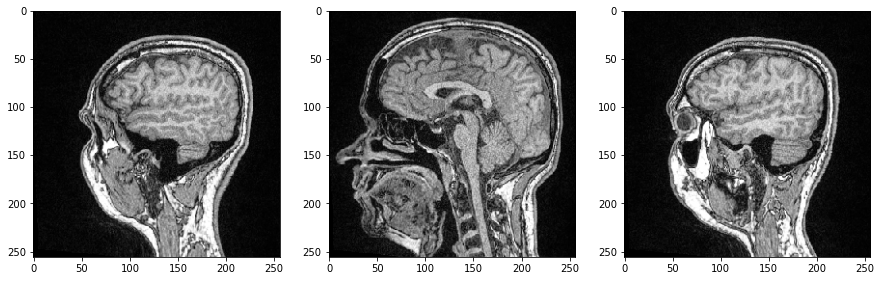

图像切片#

我们可以通过指定3D numpy数组中的索引来检查单个图像切片,这次我们使用Matplotlib的imshow进行可视化:

import matplotlib.pyplot as plt

fig, axs = plt.subplots(1, 3, figsize=(15,15))

# show three planar images

axs[0].imshow(image_stack[48], cmap='Greys_r')

axs[1].imshow(image_stack[96], cmap='Greys_r')

axs[2].imshow(image_stack[144], cmap='Greys_r');